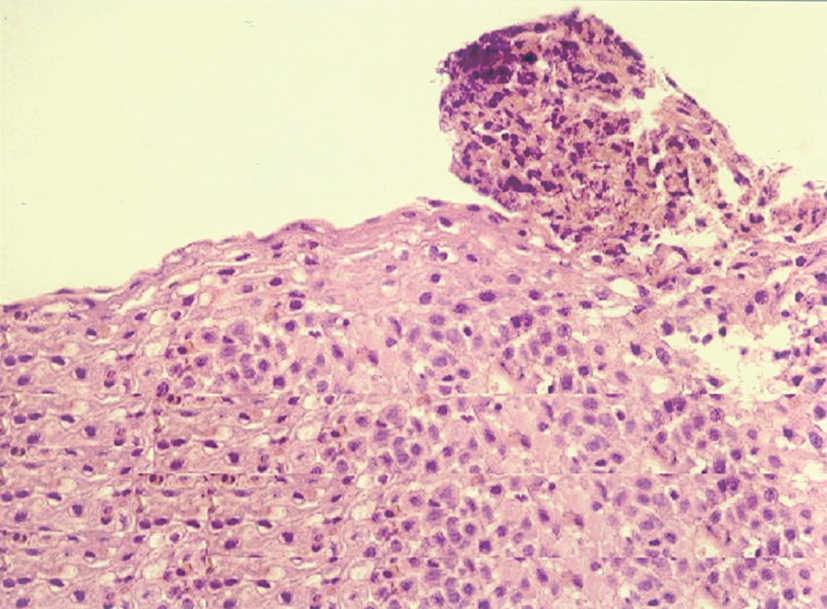

Figura 3. Microabscesos eosinofílicos que protruyen sobre la luz esofágica que se corresponden con las imágenes objetivadas en la figura 2. (Hematoxilina-eosina, x40.)

En cuanto a los hallazgos endoscópicos pueden ir desde un aspecto de la mucosa esofágica estrictamente normal a diferentes patrones de alteración endoscópica. Se ha descrito la existencia de imágenes erosivas longitudinales, granularidad, pérdida del patrón vascular, estenosis focales6, estenosis de larga extensión ("esófago de pequeño calibre")17 y fragilidad mucosa de fácil erosión al contacto con el endoscopio (denominado como crêpe paper esophagus)18. Pero el patrón que se ha comunicado con más frecuencia es el de traquealización esofágica, denominado de este modo por la presencia de imágenes de anillos transversales consecutivos que recuerdan el aspecto "corrugado" de la tráquea y que corresponderían a contracciones intermitentes de la musculatura circular esofágica19. Otra imagen bastante característica en estos pacientes es un punteado blanquecino que semeja el aspecto de candidiasis esofágica y que corresponde a acumulaciones o microabscesos constituidos por eosinófilos que protruyen sobre la superficie mucosa, como se demuestra por el estudio anatomopatológico20,21. En dos de nuestros pacientes se demostró este hallazgo.

Como hemos citado anteriormente, el hallazgo anatomopatológico característico de esta entidad es la importante infiltración eosinófila (> 20 eosinófilos por campo de gran aumento) que puede presentarse en cualquiera de sus capas, si bien predomina en la mucosa, en el epitelio peripapilar y en la lámina propia, de los tercios superior y medio esofágicos. Otros hallazgos característicos son los agregados o microabscesos de eosinófilos superficiales antes comentados, las papilas elongadas y la hiperplasia epitelial basal. Estudios ecoendoscópicos realizados en estos pacientes ponen de manifiesto el aumento en el espesor tanto de la mucosa, de la submucosa y de la muscularis mucosae, sin apreciarse cambios significativos en las capas de la musculatura circular22.